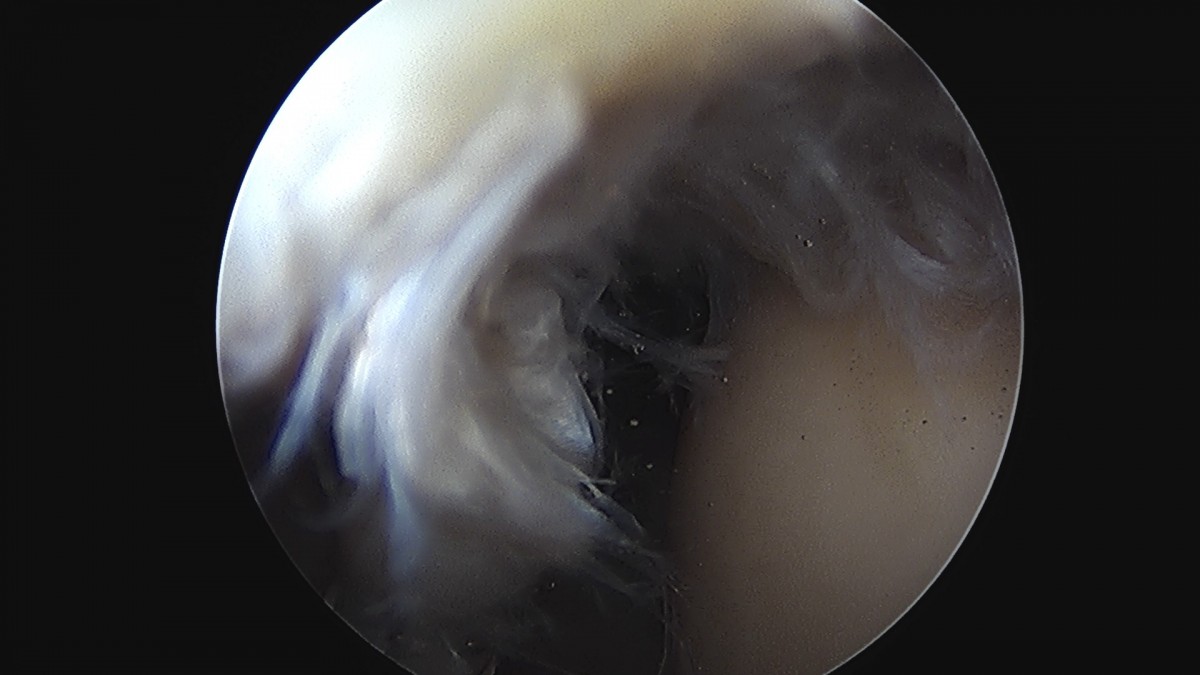

정지영원장님 어깨 회전근개 봉합술 임채O 환자

dae765e4d9ac96aee867c9d6292d8784_1758009113_696.jpg